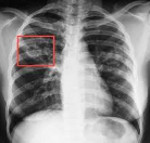

4. Туберкулема рентгенологически представляет собой округлое образование 2-5смв диаметре с четкими границами, располагающееся в 1-2 сегменте чаще справа. Это исход инфильтративного туберкулеза, когда перифокальное воспаление рассасывается и остается очаг творожистого некроза, окруженный капсулой.

• Топическая лучевая диагностика. Основным методом диагностики туберкулеза является рентгенография легких. При этом можно обнаружить очаги инфекции, как в легких, так и в других органах и тканях. При необходимости выполняют КТ легких.